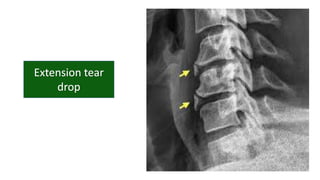

• Tear drop fracture

• #54 Last one in hyper flexion is flexion tear drop Compression fractures the ant inf column of the vertebrae Post lig dis and ant comp frac of vert body

• #55 Tear droop fragment Spinal cord compression

• No angulation

• No significant translation